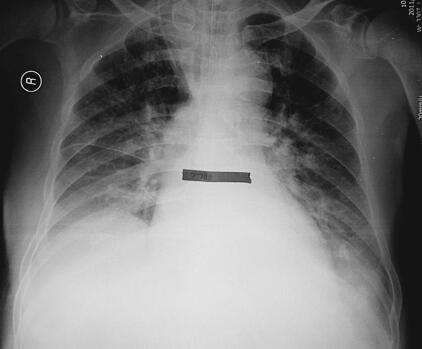

患者入院时血象明显高于正常,同时痰黄量多,体温最高38℃,给予头孢哌酮-舒巴他钠抗感染,同时经口气管插管、呼吸机辅助呼吸以及解痉平喘、祛痰等治疗。患者血象逐渐呈下降趋势,最高体温37.8℃,胸部影像亦较前明显好转,3月1日拔除经口气管插管(图3、图4)。

图4 入院第11天胸片:双肺较前明显好转